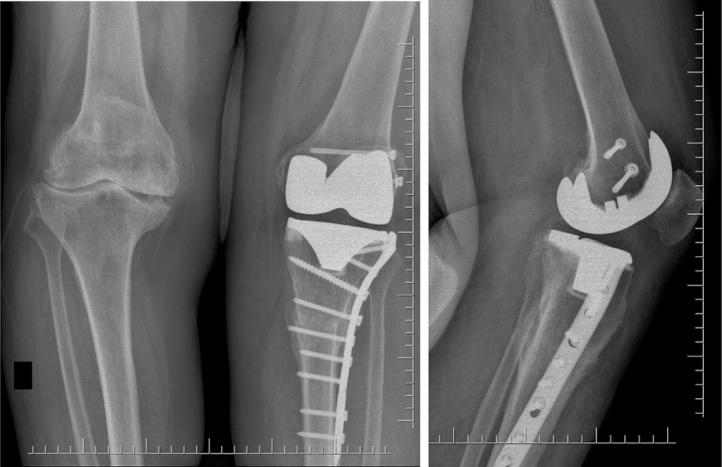

PRESENTATION OF CASE

75-year-old male patient with bilateral knee osteoarthritis had not benefited from conservative treatment methods previously applied. Left TKA was applied. In the second month postoperatively, periprosthetic tibial fracture was identified and osteosynthesis was implemented with locked tibia proximal plate-screw. Bone union in 12 weeks was observed in his follow-ups. After 15 months of his first operation, TKA was applied to the right knee. Postoperatively in the second month, as in the first operation, periprosthetic tibial fracture was detected. Osteosynthesis with locking plate-screw was applied and union in 12 weeks was observed in his follow-up. He was seen mobilized independently and without support in the last control of the case made in the 24th month after the second operation.

一名75岁男性患者患有双侧膝关节骨关节炎,之前采用的保守治疗方法均未见效。实施了左侧全膝关节置换术。术后第二个月,发现假体周围胫骨骨折,并采用锁定胫骨近端钢板螺钉进行了骨固定。随访观察到12周时骨愈合。首次手术15个月后,对右侧膝关节实施了全膝关节置换术。术后第二个月,如同首次手术一样,检测到假体周围胫骨骨折。采用锁定钢板螺钉进行骨固定,随访观察到12周时愈合。在第二次手术24个月后的最后一次病例检查中,发现他能够独立活动且无需支撑。